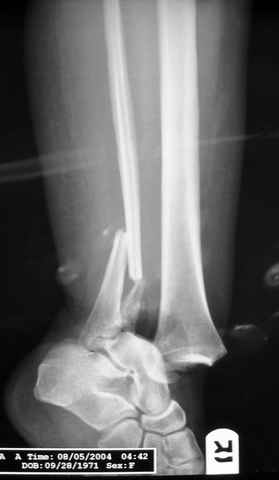

Pilon fracture:

-Появляется ориентир и остов, на чем можно строить восстановление, почему сперва малоберцовую, впервые обьяснили и описали (Pylon type and Ankle fractures) в середине 50х Rienau и Gay.

Восстановливая длину и ротацию малоберцовой кости, затем относительно легче произвести реставрацию остальных элементов перелома дистального эпиметафиза болшеберцовой кости.

где исследования на трупах показали, что малоберцовая кость участвует в стабильности голеностопного сустава, поддерживая наклон тарана (talar tilt) за счет связок. После ознакомления работой Ramsey в ортопедию ввели термин "при переломах голеностопного сустава смещенная

таранная кость следует за малоберцовой костью" т.е. связка не рвется, а тянет таран за собой, поэтому восстановление малоберцовой кости в

первую очередь, затем остальных элементов - стал классическим при лечении данной патолгии. Латеральная колонна (столб), дистальный

конец малоберцевой кости, к нему прикрепляется латеральный суставной фрагмент дистального эпиметафиза большеберцовой кости (как на снимке)

и таранная кость, которые при репозиции малоберцовой кости репонируются автоматически.